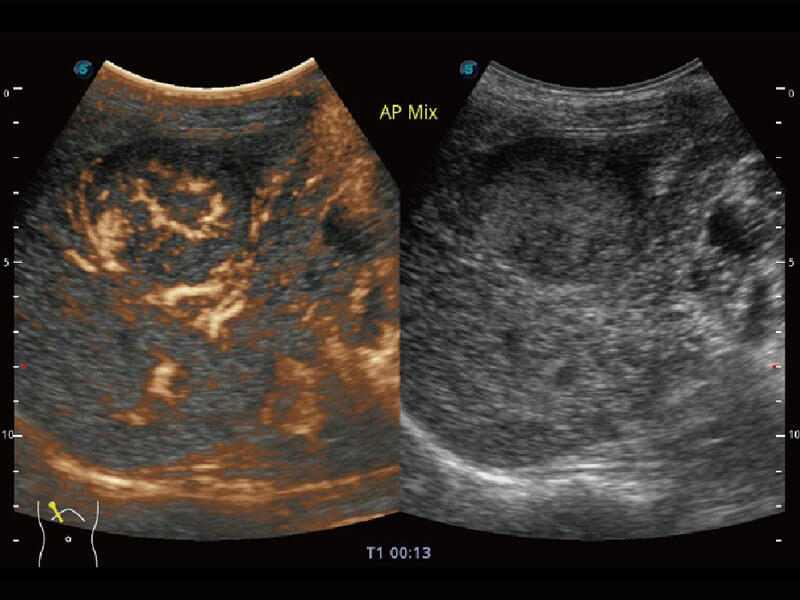

超宽频带技术,为容积成像带来优质的二维图像基础,为您呈现丰富的结构细节,栩栩如生地展示宝宝的宫内形态以及各种组织的立体结构。

Micro F 显微血流成像 明察秋毫